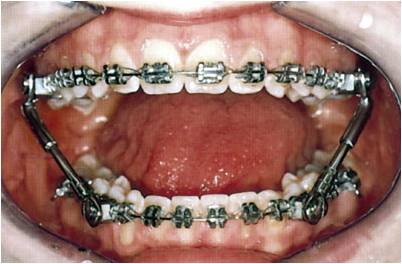

Was für Behandlungsgeräte gibt es?

Man unterscheidet zwischen herausnehmbaren und festsitzenden Apparaturen.

Da es eine Vielzahl an Behandlungsgeräten gibt und diese für jeden Patienten individuell verschieden sind, wird hier nur eine kleine Übersicht gezeigt.

Welche Geräte während einer kieferorthopädischen Behandlung zum Einsatz kommen, entscheidet der Kieferorthopäde nach Auswertung der diagnostischen Unterlagen.